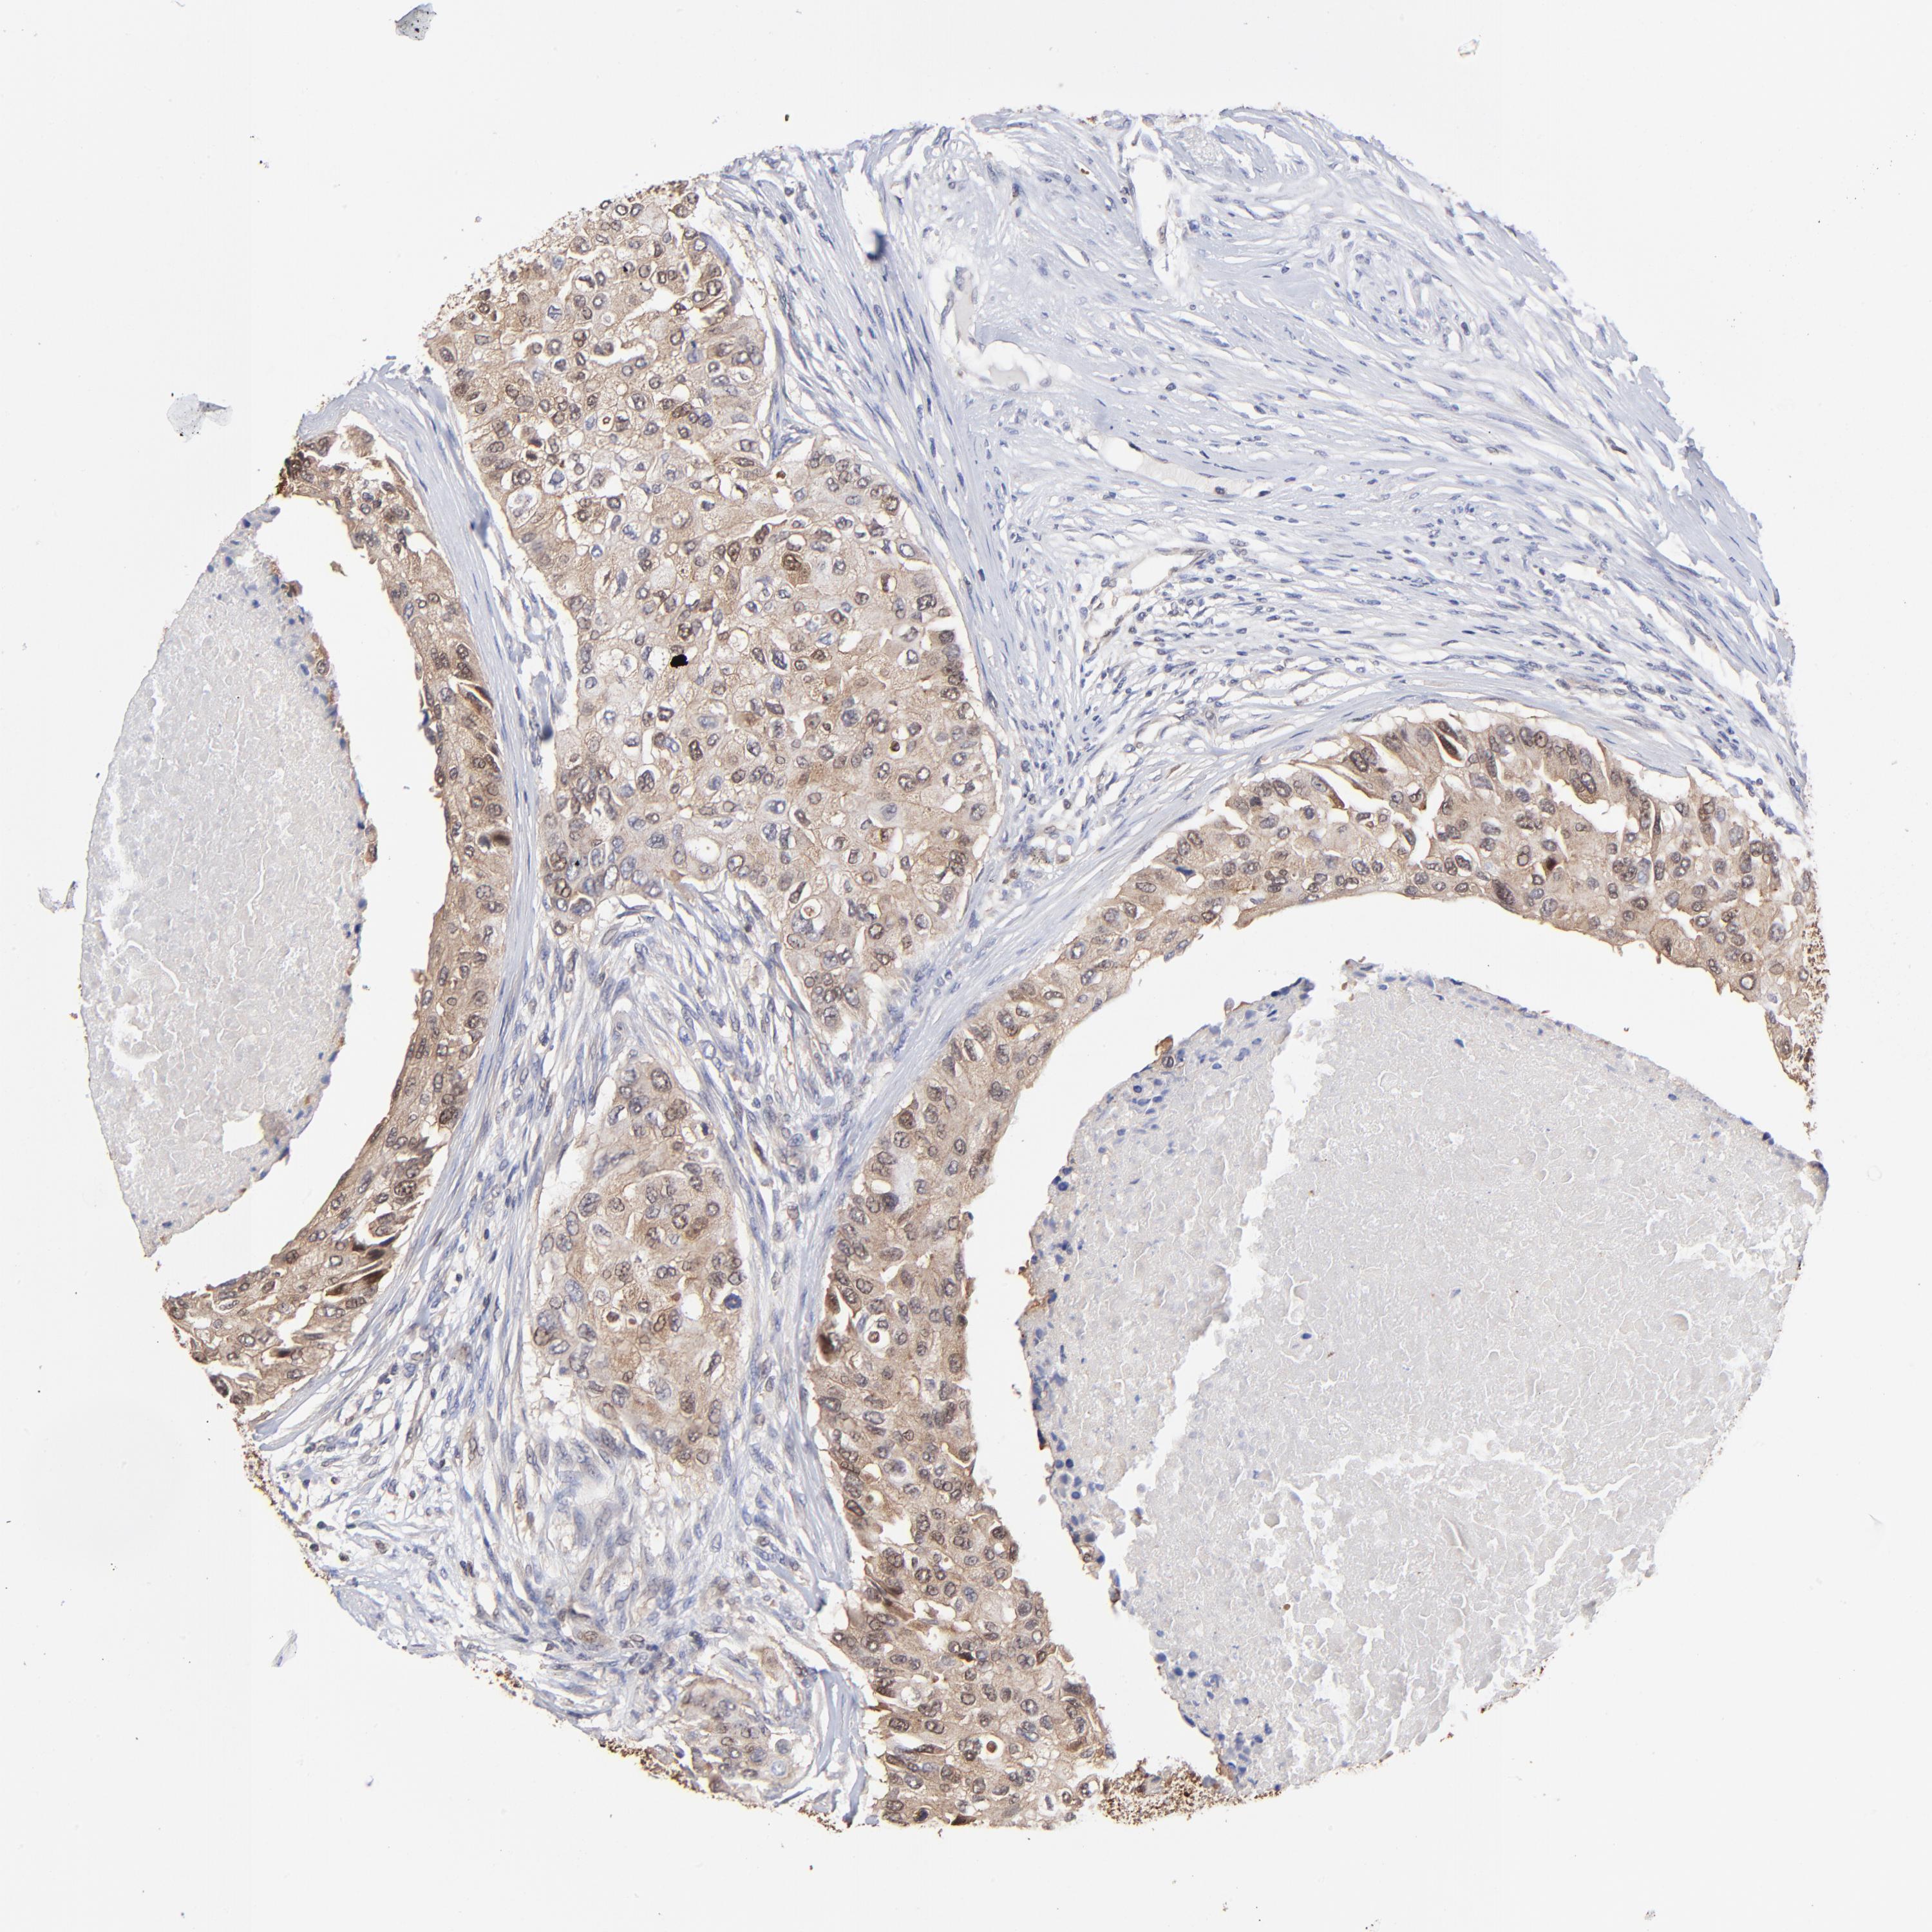

BRCA TCGA BRCA VALIDATION PROTEIN EXPRESSION

ANTIBODIES

AND

VALIDATION